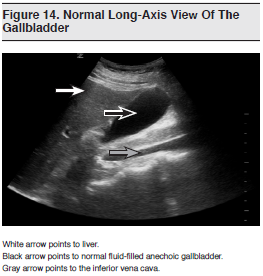

The most commonly used imaging modality in suspected cholecystitis is right upper quadrant (RUQ) ultrasound. (See Figures 14 and 15) Radiology-performed ultrasound has good sensitivity (88% to 94%) and specificity (78% to 80%) and is more convenient than radionuclide scanning, without the radiation exposure of CT.110 In comparison with comprehensive radiology-performed ultrasound, emergency clinician–performed focused RUQ ultrasound describes a focused ultrasound performed at the patient’s bedside and designed to answer targeted questions. It has excellent comparative sensitivity and specificity, can be performed and interpreted at the bedside, and has been shown to decrease ED length of stay.

Although there are many sonographic criteria for acute cholecystitis (including gallstones, sonographic Murphy’s sign, gallbladder wall thickening greater than 4 mm, pericholecystic fluid, and common bile duct dilation), gallstones are present in over 90% of cases of acute cholecystitis.112 A radiology-performed study of 497 patients found the combination of gallstones with a positive sonographic Murphy’s sign had a positive predictive value of 92%, and the combination of gallstones with a thickened gallbladder wall had a positive predictive value of 95% in diagnosing acute cholecystitis.113 Hence, many studies of ED ultrasound of the gallbladder have focused on the presence of gallstones. This finding, along with a sonographic Murphy’s sign or thickened gallbladder wall, can then be considered in conjunction with the clinical presentation and laboratory findings.